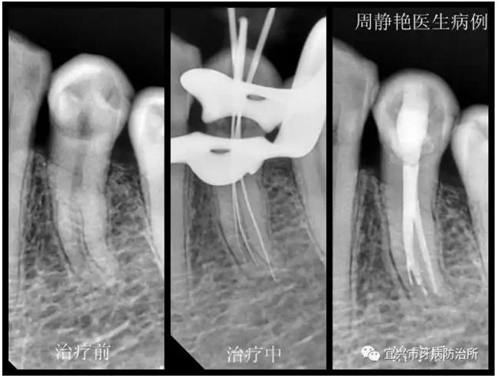

患者鄭女士,61歲,一個(gè)月以來(lái),左下后牙經(jīng)常冷熱刺激痛,一周來(lái)疼痛加劇,夜間痛明顯,冷刺激更甚。經(jīng)X光檢查,34根尖無(wú)明顯陰影,根管形態(tài)復(fù)雜,疑是根中分為雙根管或C形根管。上障,34局麻下去腐,開(kāi)髓,拔髓,根管探查,疑是3根管,拍診斷絲片。再次根管蕩洗,熱牙膠充填,流動(dòng)樹(shù)脂墊底,樹(shù)脂充填。囑一月后復(fù)查,冠修復(fù)。